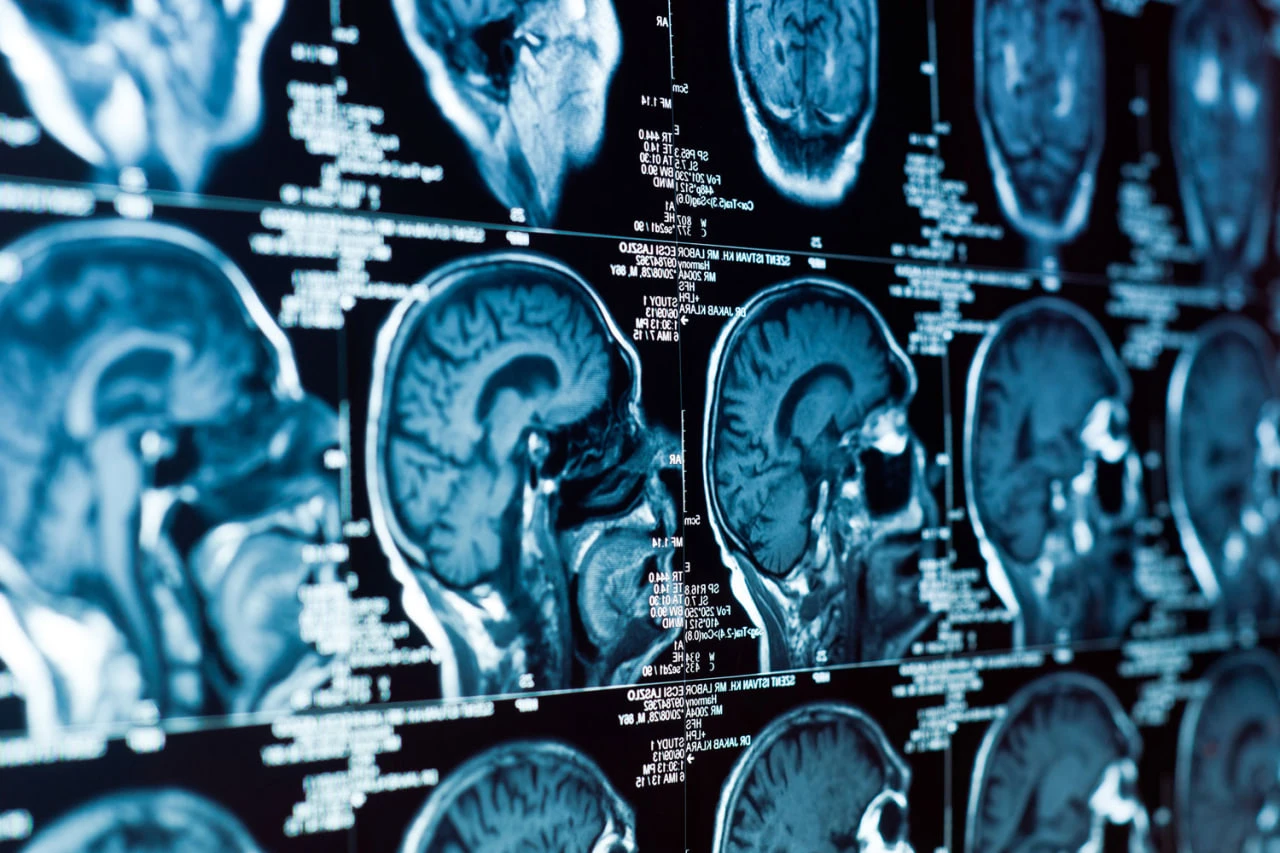

يعطل مرض الزهايمر إيقاعات الساعة البيولوجية لخلايا الدماغ المسؤولة عن إزالة اللويحات السامة. توصل علماء من كلية الطب بجامعة واشنطن إلى هذا الاستنتاج. ونشرت الدراسة في مجلة Nature Neuroscience (NatNeuro).

ووجد الفريق، بقيادة عالم الأعصاب إريك موزيك، أن لويحات الأميلويد، وهي سمة رئيسية للمرض، تعطل وظيفة مئات الجينات التي تنظم إيقاعات الساعة البيولوجية للخلايا الدبقية الصغيرة والخلايا النجمية. تعمل هذه الخلايا بمثابة "منظفات" للدماغ. تعمل الخلايا الدبقية الصغيرة على تنظيف الأنسجة من السموم والخلايا الميتة، بينما تحافظ الخلايا النجمية على وظيفة الخلايا العصبية.

وفي التجارب التي أجريت على الفئران، أظهر الباحثون أنه عندما يتراكم الأميلويد، تتعطل الإيقاعات الطبيعية لنشاط الجينات في هذه الخلايا، مما يحول النظام المنظم إلى نظام فوضوي. ونتيجة لذلك، يتم تعطيل النشاط المتزامن للآليات المسؤولة عن إزالة الأميلويد. علاوة على ذلك، يخلق الأميلويد "إيقاعات جديدة" في مئات الجينات الأخرى المرتبطة بالالتهاب.